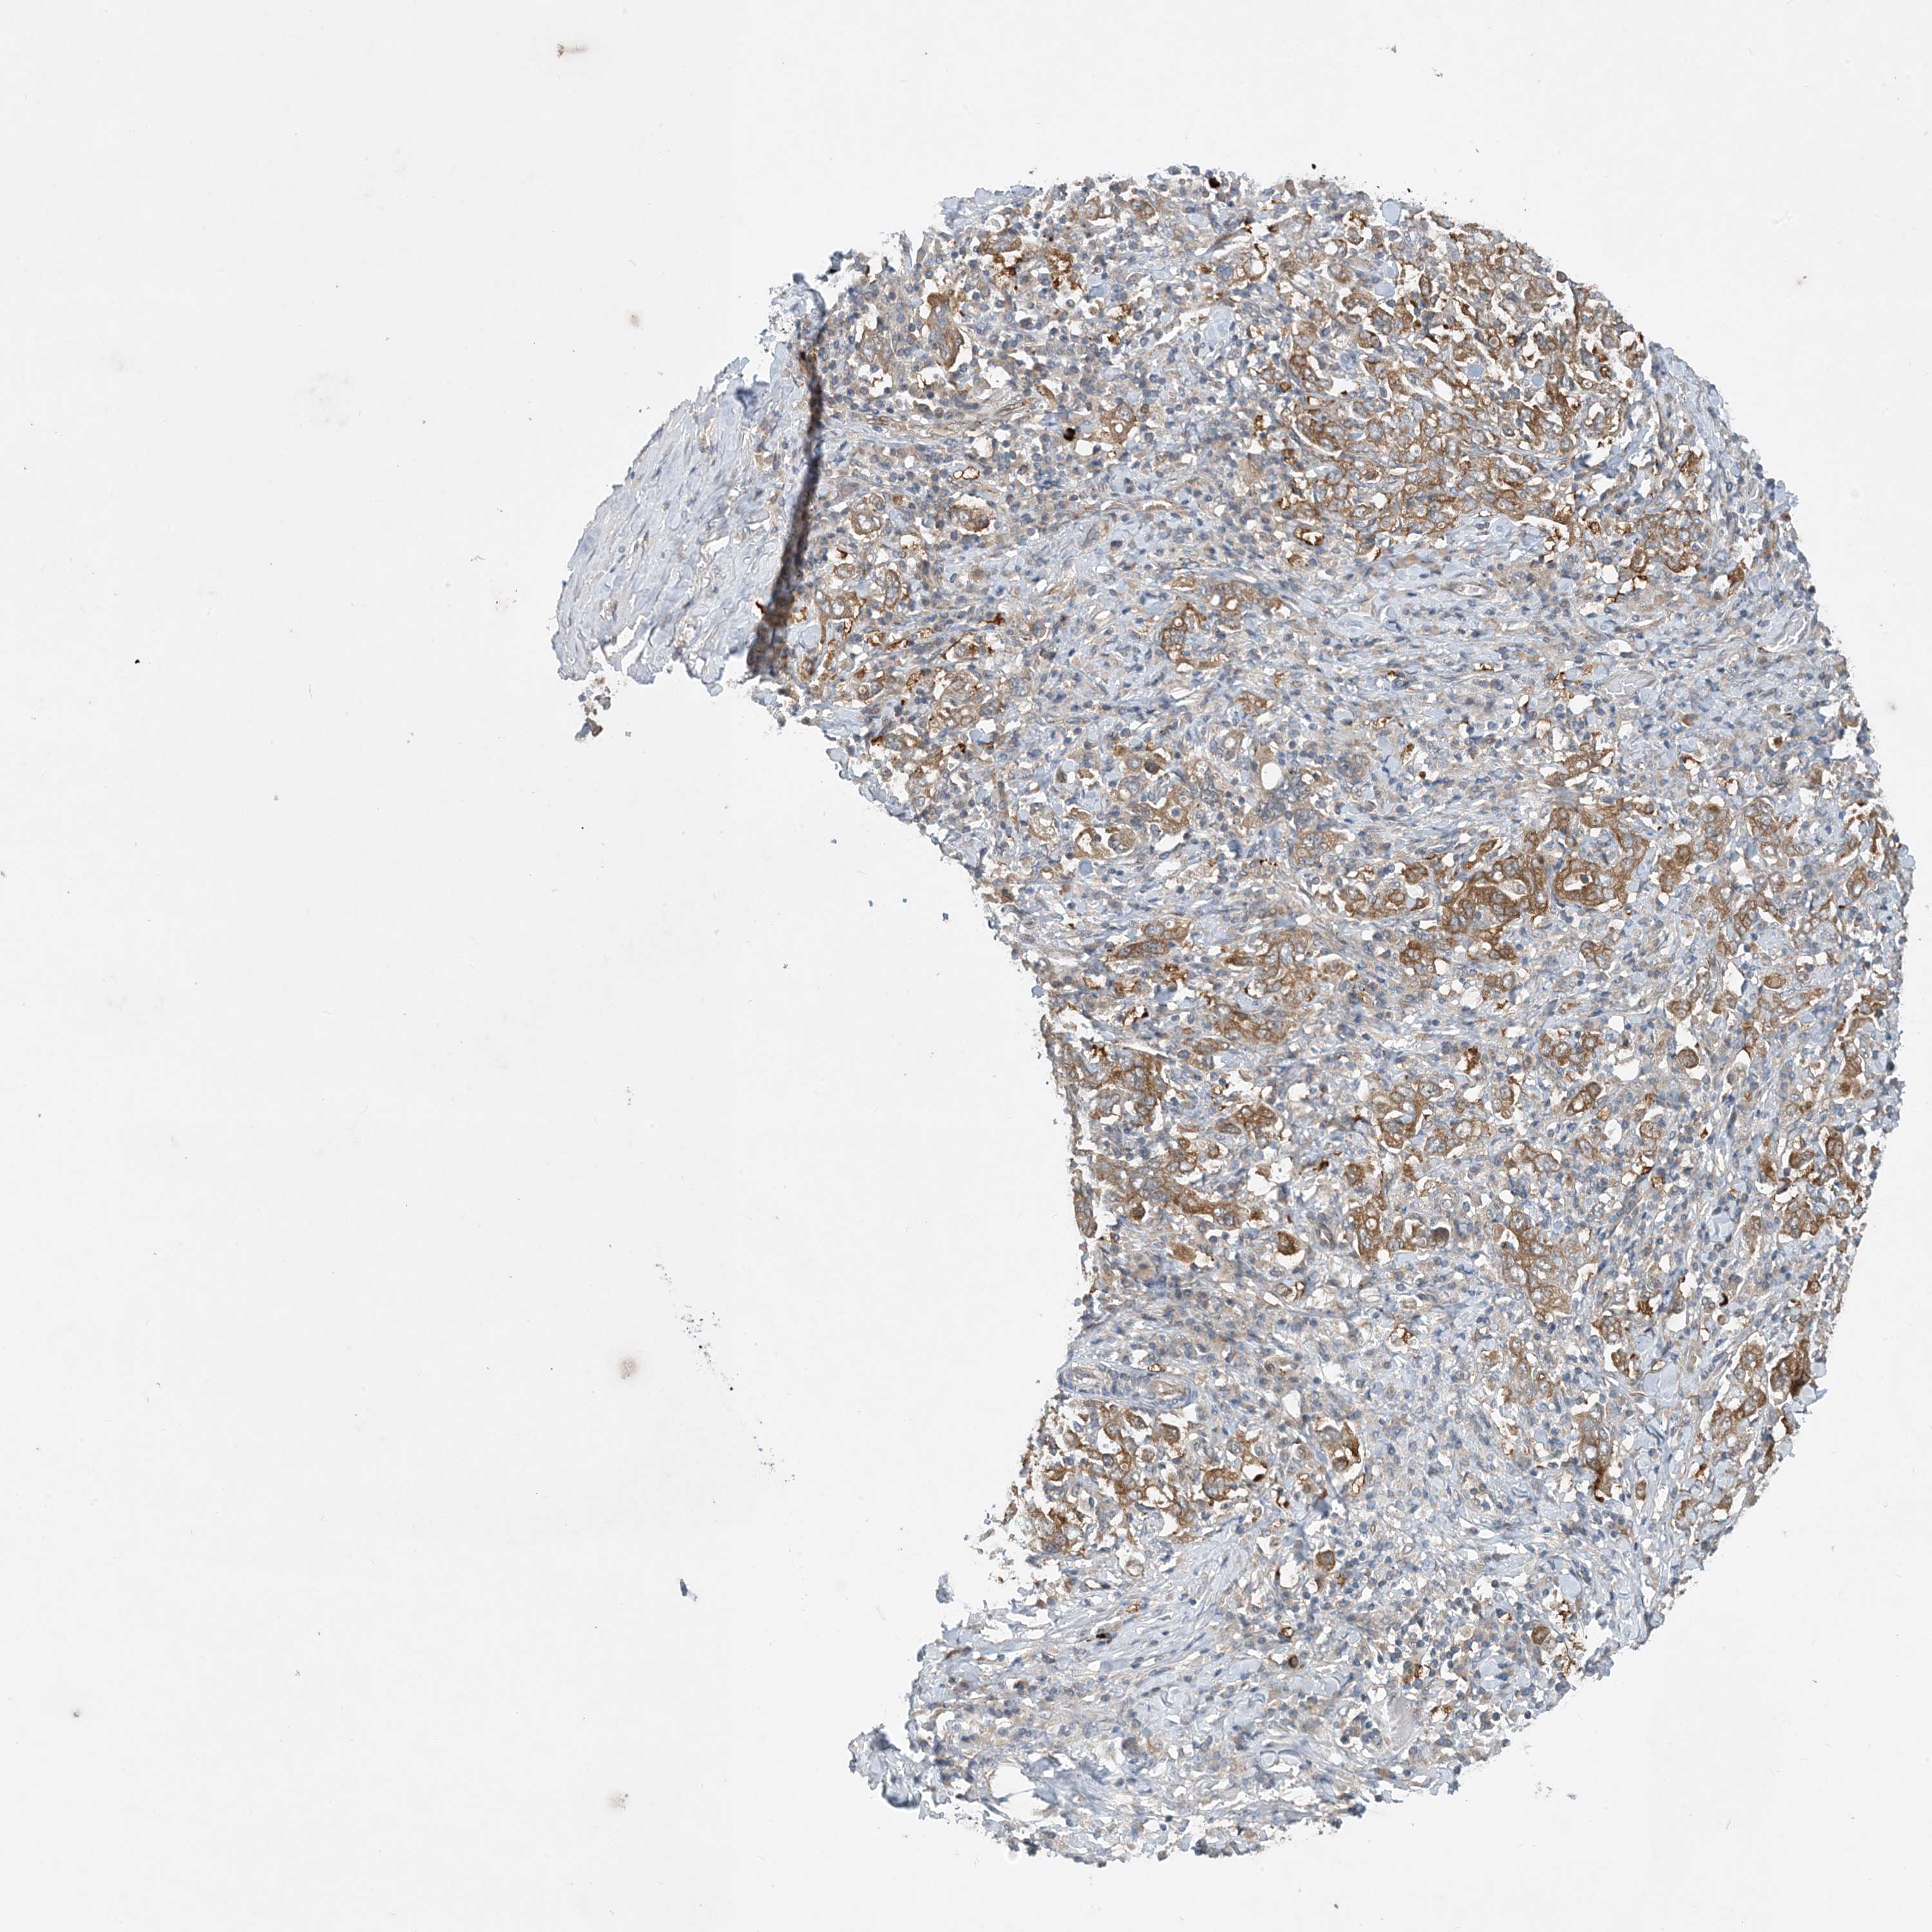

STOMACH CANCER - Protein expressioni

A mouse-over function shows sample information and annotation data. Click on an image to view it in a full screen mode. Samples can be filtered based on level of antibody staining by selecting one or several of the following categories: high, medium, low and not detected. The assay and annotation is described here.

Note that samples used for immunohistochemistry by the Human Protein Atlas do not correspond to samples in the TCGA dataset.

Antibody stainingi

Antibody staining in the annotated cell types in the current human tissue is reported as not detected, low, medium, or high, based on conventional immunohistochemistry profiling in selected tissues. This score is based on the combination of the staining intensity and fraction of stained cells.

Each image is clickable and will lead to virtual microscopy that enables deeper exploration of all samples and also displays staining intensity scores, fraction scores and subcellular localization as well as patient and tissue information for each sample.

Antibody HPA035427

Antibody HPA073753

Staining

High

Medium

Low

Not detected

Intensity

Strong

Moderate

Weak

Negative

Quantity

>75%

75%-25%

<25%

None

Location

Nuclear

Cytoplasmic/membranous

Cytoplasmic/membranous,nuclear

Adenocarcinoma, NOS

Adenocarcinoma, High grade